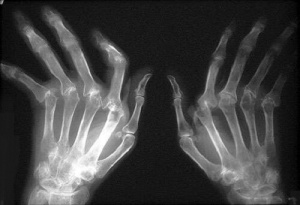

De främsta och mest synliga symptomen är svullnad eller inflammation av lederna, vilket orsakar mycket smärta. De områden som påverkas mest av ledgångsreumatism är handleder, armbågarna, axlarna, fingrarna, tårna, höfterna, anklarna och dina knän. Det är vanligt att de patienter som har denna sjukdom har en känsla av stelhet, speciellt då de vaknar upp på morgonen.

Reumatiska knutor kan också uppkomma. Dessa visar sig som bulor på skinnet (speciellt på baksidan av händer och fötter) eller inuti kroppen. Inflammationen orsakar en missformning av lederna då sjukdomen når ett visst tillstånd.

Andra symptom som personer med ledgångsreumatism har är feber, utmattning, torrhet i slemhinnor (mun, ögon etc.), nacksmärtor och stickningar i händer och fötter.